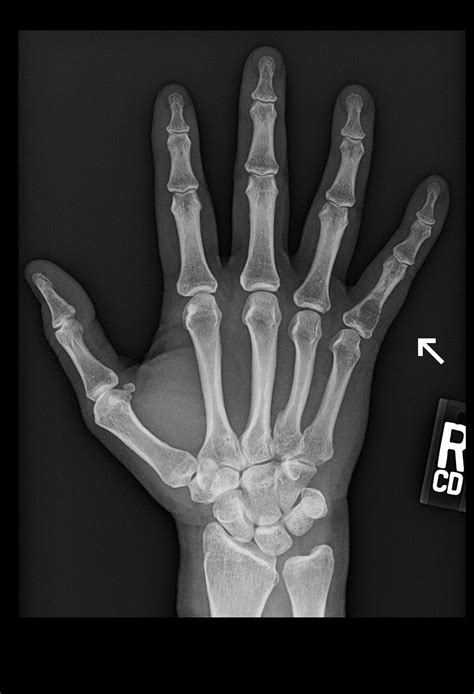

Diagnosing a Dislocated Small Finger

If you suspect a dislocated small finger, it is crucial to seek medical attention promptly. A healthcare professional will perform a physical examination and may order imaging tests to confirm the diagnosis. Common diagnostic methods include:

• X-rays: To visualize the bones and determine the extent of the dislocation.

• MRI or CT Scans: In some cases, these advanced imaging techniques may be used to assess soft tissue damage.